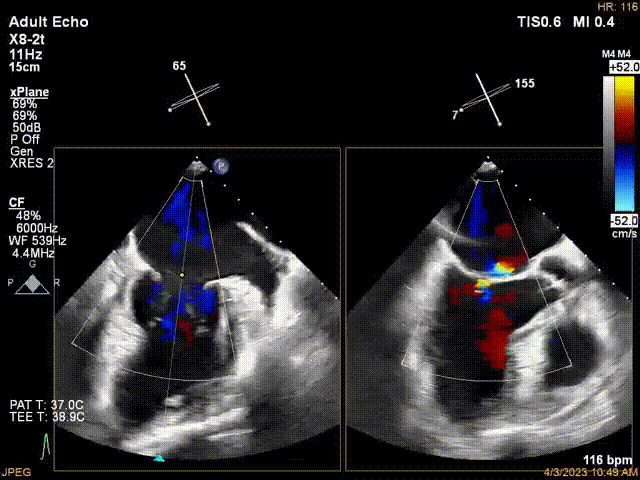

術(shù)前超聲提示二尖瓣重度反流

接受治療的是一例器質(zhì)性重度二尖瓣反流(DMR)患者,主訴“反復(fù)活動后胸悶,氣促3年余”。術(shù)前超聲顯示,雙房增大,二尖瓣脫垂伴重度反流,輕度三尖瓣反流,輕度肺高壓,升主動脈增寬。手術(shù)經(jīng)股靜脈-房間隔入路,采用全身麻醉插管,在TEE和DSA引導(dǎo)下完成房間隔穿刺。置入JensClip瓣膜夾系統(tǒng)后,在左房調(diào)整瓣膜夾的位置和軸向,后進(jìn)入左室,在TEE引導(dǎo)下捕捉二尖瓣前后瓣葉,并關(guān)閉瓣膜夾。經(jīng)TEE反復(fù)確認(rèn)手術(shù)效果后最終鎖定并釋放瓣膜夾。術(shù)后即刻超聲顯示瓣膜夾位置穩(wěn)定,功能良好,術(shù)前二尖瓣反流4+,術(shù)后0反流,肺靜脈逆流和左房壓都顯著好轉(zhuǎn),手術(shù)圓滿成功(以上數(shù)據(jù)都來源于醫(yī)院的臨床記錄)。術(shù)后患者狀態(tài)良好,目前已安排出院。